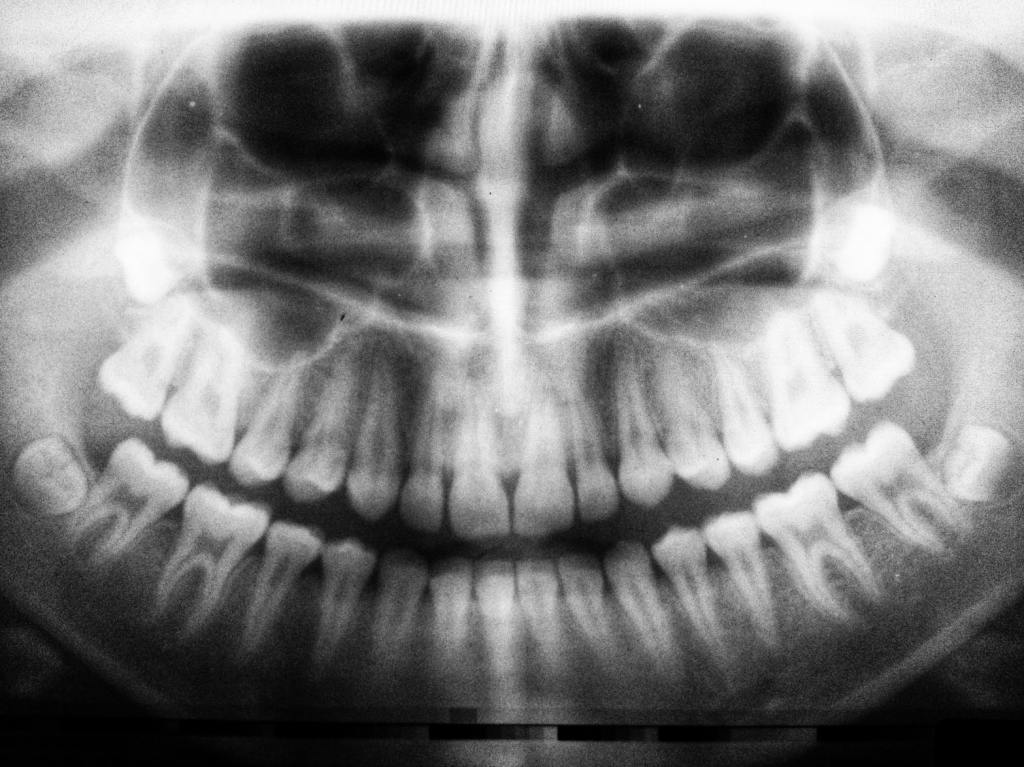

ブラジル便り#14 歯形 2020-06-15未分類硬派くん ・長崎・熊本 ・在日韓国人 ・歯医者での会話 ・23andme 共有: X で共有 (新しいウィンドウで開きます) X その他 友達にメールでリンクを送信 (新しいウィンドウで開きます) メールアドレス いいね 読み込み中…